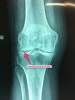

- 방사선 소견 : meniscus에 점상, 선형은 chondrocalcinosis